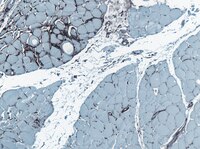

The human thymic microenvironment. Phenotypic characterization of Hassall's bodies with the use of monoclonal antibodies.

The human thymic microenvironment is important in promotion of T cell maturation, particularly during early stages of thymic ontogeny. Hassall's bodies (HB) are epithelial swirls in the human thymic medulla that are thought to be derived from endocrine medullary thymic epithelium. To study the ontogeny and function of various components of the human thymic microenvironment, we have produced four monoclonal antibodies (TE-8, TE-15, TE-16, and TE-19) that selectively reacted in thymus with HB. Antibodies TE-8 and TE-16 reacted with the cells forming the outer rim of the HB swirl. Antibody TE-19 reacted with the entire cellular portion of HB and with epithelial cells immediately surrounding HB. Granular foci in the cellular swirls of greater than 90% of HB reacted with antibody TE-15. During thymic ontogeny, the antigens defined by antibodies TE-8, TE-15, TE-16, and TE-19 were first detected in fetal thymus on HB beginning at 16 wk gestation, the age when HB morphologically appear in the thymus. Aberrant expression of the antigens corresponding to antibodies TE-8, TE-15, TE-16, and TE-19 was observed on thymic tissue from individuals with severe cellular immunodeficiency disease. In human skin, antibodies TE-8, TE-16, and TE-19 reacted with the stratum granulosum; antibody TE-15 reacted with the stratum corneum. Thus, with the use of antibodies TE-8, TE-15, TE-16, and TE-19, we have identified HB as antigenically distinct regions of endocrine thymic epithelium. Furthermore, we have shown that these anti-HB reagents also selectively react with epidermal keratinocytes in the terminal stages of keratinocyte maturation. | 2578044